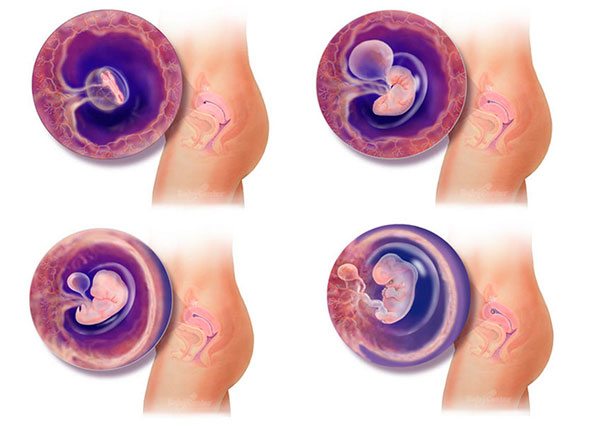

Развитие эмбриона: Что происходит на 3 неделе беременности

Раздел: Фотопанорама